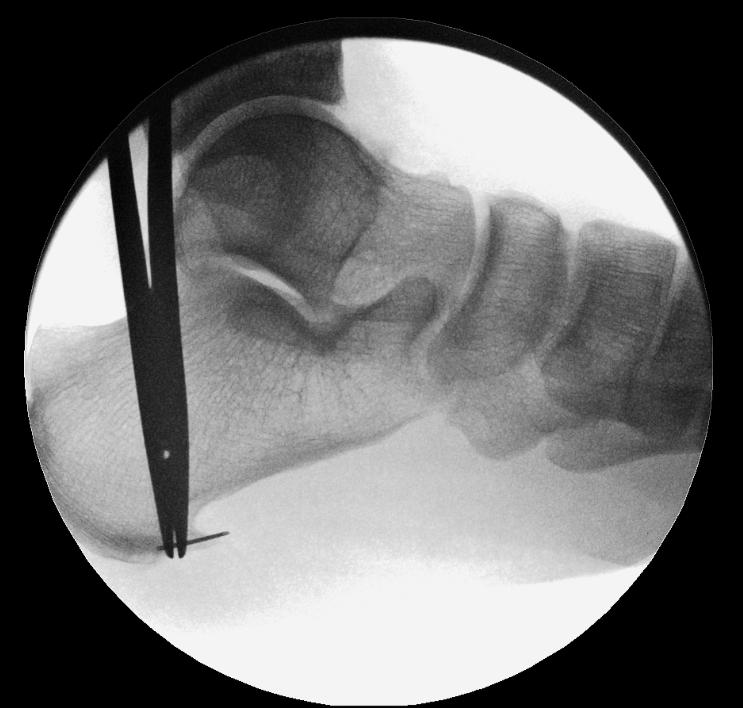

Procedure

This is a supra-fascial technique. A needle is used under fluoroscopy to identify the spur. Through a medial incision, blunt entry of the trocar is made at about a 30° angle. The lateral portal is identified by tenting the lateral skin (Figure 1).

A 4.0mm scope is inserted medially, above the plantar fascia, and instruments introduced laterally (Figure 2).

Visualization of the plantar fascia and the plantar heel spur is achieved (Figure 3).

Synovial debridement is achieved with an arthroscopic shaver or radiofrequency ablation to achieve haemostasis. The calcaneal spur is burred until no longer prominent or impinging on the fascia. Imaging may be used to confirm.

The medial third of the plantar fascia is released with arthroscopic scissors or a radiofrequency probe (Figures 4 & 5).

Radiofrequency micro-tenotomy is performed to cover the entire footprint

1

Figure

of the proximal plantar fascia (e.g. Smith & Nephew Topaz XL tendon Microdebrider) (Figure 6).